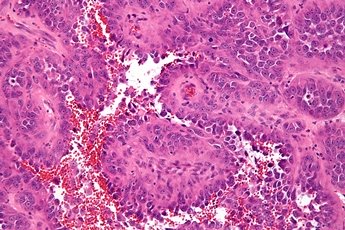

Диагноз ставится на основании биопсии (небольшой сегмент опухоли удаляют из организма и исследуют под микроскопом), изучения ультраструктурных и гистохимических маркеров. Большая часть ангиосарком является высоко злокачественными опухолями, быстро растут и распространяются. Раннее обнаружение с помощью данного метода дает высокие шансы на излечение.